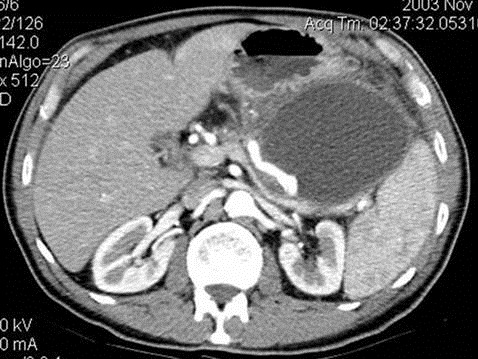

Nang giả tụy. Phương pháp phổ biến và hiệu quả nhất để chẩn đoán nang giả tụy là chụp cắt lớp vi tính. Nang giả thường xuất hiện dưới dạng một khối chứa đầy dịch

Nang giả tụy. Phương pháp phổ biến và hiệu quả nhất để chẩn đoán nang giả tụy là chụp cắt lớp vi tính. Nang giả thường xuất hiện dưới dạng một khối chứa đầy dịch. Trong một số trường hợp, bác sĩ phải sử dụng các phương pháp khác để phân biệt nang thật và nang giả, thường là bằng siêu âm qua ngã nội soi hoặc chọc hút bằng kim nhỏ. Siêu âm bụng có thể xác định được nang giả, có dạng hình tròn và có một lớp bao bọc bên ngoài. Nang giả có hình dạng phức tạp hơn khi còn nhỏ, khi xuất huyết hoặc có biến chứng do nhiễm trùng. Chụp cắt lớp vi tính chính xác hơn và cung cấp chi tiết hơn các nang giả cũng như môi trường xung quanh nang giả. Tuy nhiên, điểm yếu của phương pháp này là khó phân biệt được nang thật và nang giả. Hơn nữa, chất cản quang tĩnh mạch đưa vào lúc chụp cắt lớp vi tính có thể làm trầm trọng thêm tình trạng rối loạn chức năng thận. Bên cạnh đó, chụp cộng hưởng từ và chụp đường mật cộng hưởng từ cũng là phương pháp hiệu quả để phát hiện nang giả nhưng không được sử dụng thường xuyên vì chụp cắt lớp vi tính đã cung cấp hầu hết các thông tin cần thiết. Tuy nhiên, chụp cộng hưởng từ và chụp cộng hưởng từ đường mật lại cung cấp độ tương phản tốt hơn, giúp thấy rõ đặc tính của chất dịch, các mảnh vụn và phát hiện tình trạng chảy máu. Ngoài ra, bác sĩ thường sử dụng nội soi qua siêu âm như là một xét nghiệm thứ cấp để đánh giá thêm các nang được tìm thấy trong các xét nghiệm khác và muốn xác định xem nang có phải là giả hay không;